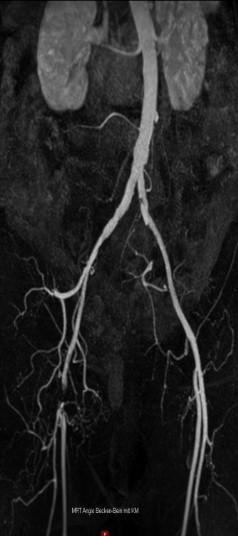

MR-Angiografiya (Şəkil 1):

- Sağ A. femoralis communis-in tam tutulmas

- AFS və APF kollaterallar vasitəsilə yenidən qanla dolu

- Aşağı hissədə yüksək dərəcəli daralmalar yoxdur, yaxşı üçdamarlı qan axını mövcuddu

- Sol tərəf: patologiya aşkar edilməyib

Şəkil 1.Çanaq və ayaq arteriyalarının MR-angiografiyası sağ A. femoralis communis-in tıxanmasını göstərir. A. femoralis superficialis və A. profunda femoris açıqdır.Sağ tərəfdə baldırın yuxarı hissəsində (proksimal hissəsində) üç damarla təchizat mövcuddur.Baldırın aşağı hissəsində (distal hissəsində) venoz strukturların üst-üstə düşməsi bu sahənin qiymətləndirilməsini məhdudlaşdırır.